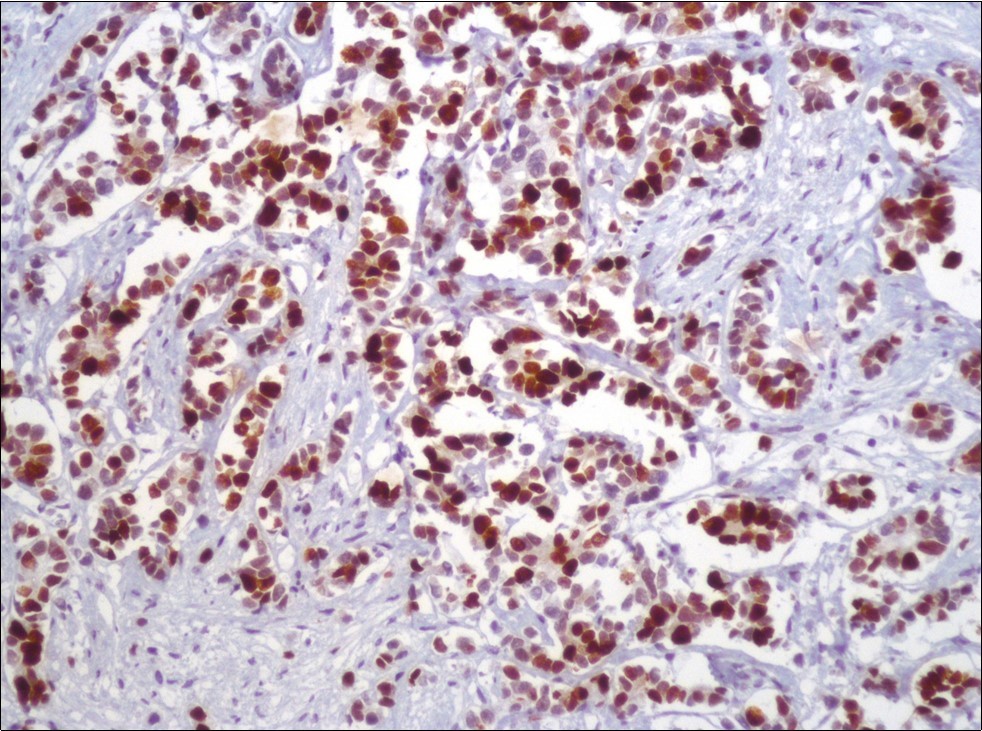

A 73-year-old male patient was admitted to our outpatient clinic with acute urinary retention. Digital rectal examination was normal. The PSA value was 1.81 ng/dl. Prostate size was 101 cc. Since the PSA value and digital rectal examination were normal, no biopsy was taken. Ultrasonography showed bilaterally ureterohydronephrosis. The creatinine level was 2.89 mg/dl. Hypertension has been presented as a comorbidity. An 18 Fr Foley catheter was inserted and alpha-blockers and 5-α reductase inhibitor medication was given. Creatinine level decreased to 0.91 mg/dl after one week. When the patient's catheter was pulled out, he could not urinate again. A catheter was inserted and waited one week more. After one week, the patient was unable to urinate again. The operation was decided due to this recurrent urinary retention. Because of prostate size was 101 cc and prostatic urethra was long, open prostatectomy was decided. When the prostate was removed during the operation, it was evaluated that the left side and the lower side were adhered to surrounding tissue. The prostate was removed as an en bloc. The catheter was removed after 5 days. The pathology of the patient has been reported as pure small cell prostate carcinoma. On the microscopic examination, the tumor was heavily infiltrated into the prostate parenchyma (Figure 1). Tumor cells were consist of atypical small-medium sized, mitotically active cells with a high nuclear to cytoplasmic ratio, hyperchromatic nucleus, nuclear molding, and inconspicuous nucleoli (Figure 2). On the immunohistochemically examination of synaptophysin showed diffusely and strong positivity while chromogranin A showed focal weak positivity with the absence of staining for PSA (Figure 3). Ki67 proliferative index was equal to 90% of the tumor cells (Figure 4). The results confirmed the diagnosis of prostatic small cell carcinoma. Metastatic lymph nodes were detected in the right perirectal region with metastatic multiple lymph nodes in the bilateral external iliac region, more on the left than in the PET CT. No metastasis was detected in the brain MRI and thorax computed tomography. Four cycles of etoposide and cisplatin chemotherapy were administered to the patient. Control PET CT taken after chemotherapy showed a significant decrease in size and metabolic activity of the right obturator and lymph nodes in the right perirectal area. The size and metabolic character of the left obturator, left external iliac and common iliac lymph nodes were increased. After a month, patient admitted to emergency outpatient clinic with left flank pain. There was an 8-cm mass in retroperitoneal area in the computed tomography. Supportive treatment was started because the patient could not tolerate chemotherapy. The masses reached to 13x11cm and fulfilled the retroperitoneal area. Multiple lung metastases were seen. The patient died 13 months later after the first diagnosis.